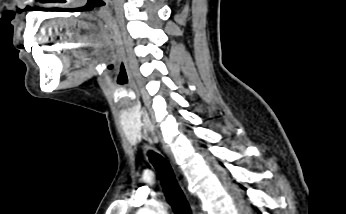

КТ щитовидной железы часто используется в диагностике доброкачественных и злокачественных опухолей железы, оценки распространенности процесса, поэтому для улучшения визуализации патологических очагов дополнительно применяется внутривенное болюсное контрастирование. Методика контрастирования позволяет увидеть на снимке опухоли минимальных размеров за счет того, что контраст избирательно накапливается в измененных тканях и обеспечивает яркое изображение патологического очага на фоне здоровых окружающих тканей.  Контрастирование дает возможность определить врачу границы опухоли, ее размеры, степень васкуляризации, точное расположение, особенно это важно при нетипичной (загрудинной) локализации органа.

В наших центрах обследование щитовидной железы выполняется на современных мультиспиральных томографах TOSHIBA AQUILION, оснащенных увеличенным количеством сверхчувствительных детекторов, позволяющих производить множество срезов с минимальной толщиной от 0,5 мм. Инновационные возможности аппаратов обеспечивают получение множества послойных снимков высокого качества и построение на их основе трехмерной модели органа. Кроме того, аппаратура позволяет за счет сокращения времени сканирования минимизировать лучевую нагрузку на пациента.

Мультиспиральная компьютерная томография позволяет точно определить размеры и расположение щитовидной железы, выявить опухолевые образования, оценить их структуру, степень кровоснабжения, взаимодействие с окружающими тканями.